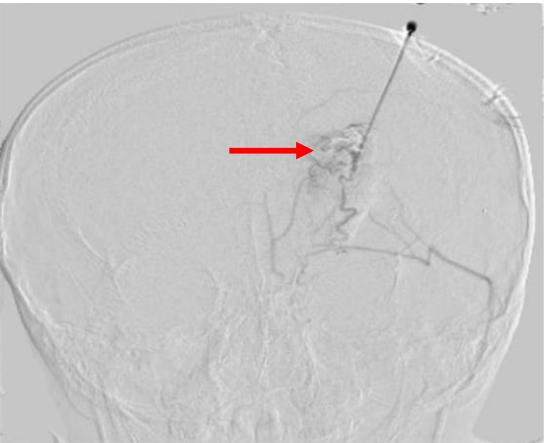

图1 患儿临床资料:A.箭头指示患儿左额部包块 B.箭头指示血管造影下左额部畸形血管团(瘤巢)

11岁的小强(化名)父母亲从小便发现他左侧额头部有一包块,并未引起重视,近4年以来包块逐步增大,可见到包块周围“青筋暴露”,可扪及波动感(图1A)。小强父母很着急,带着他辗转多家医院后来到省医小儿外科门诊就诊,完善增强CT检查显示左额部畸形血管团,医生考虑诊断左额部动静脉畸形,小强被安排住进小儿外科病房。